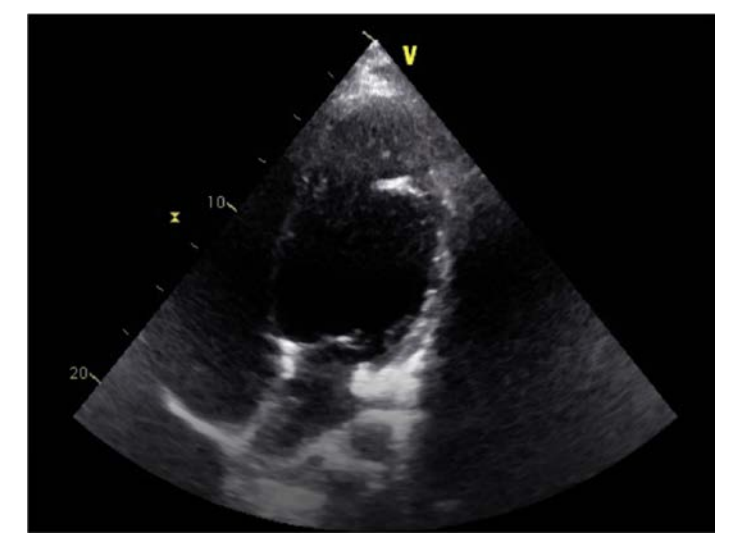

o Echo in September 2015 also revealed severe global LV hypokinesis with an estimated ejection fraction (EF) of 20-25% and an LV thrombus.

o Echo revealed a mild change in EF to 30% from 20-25% in 2015 and an unchanged LV thrombus seen on the previous echo.